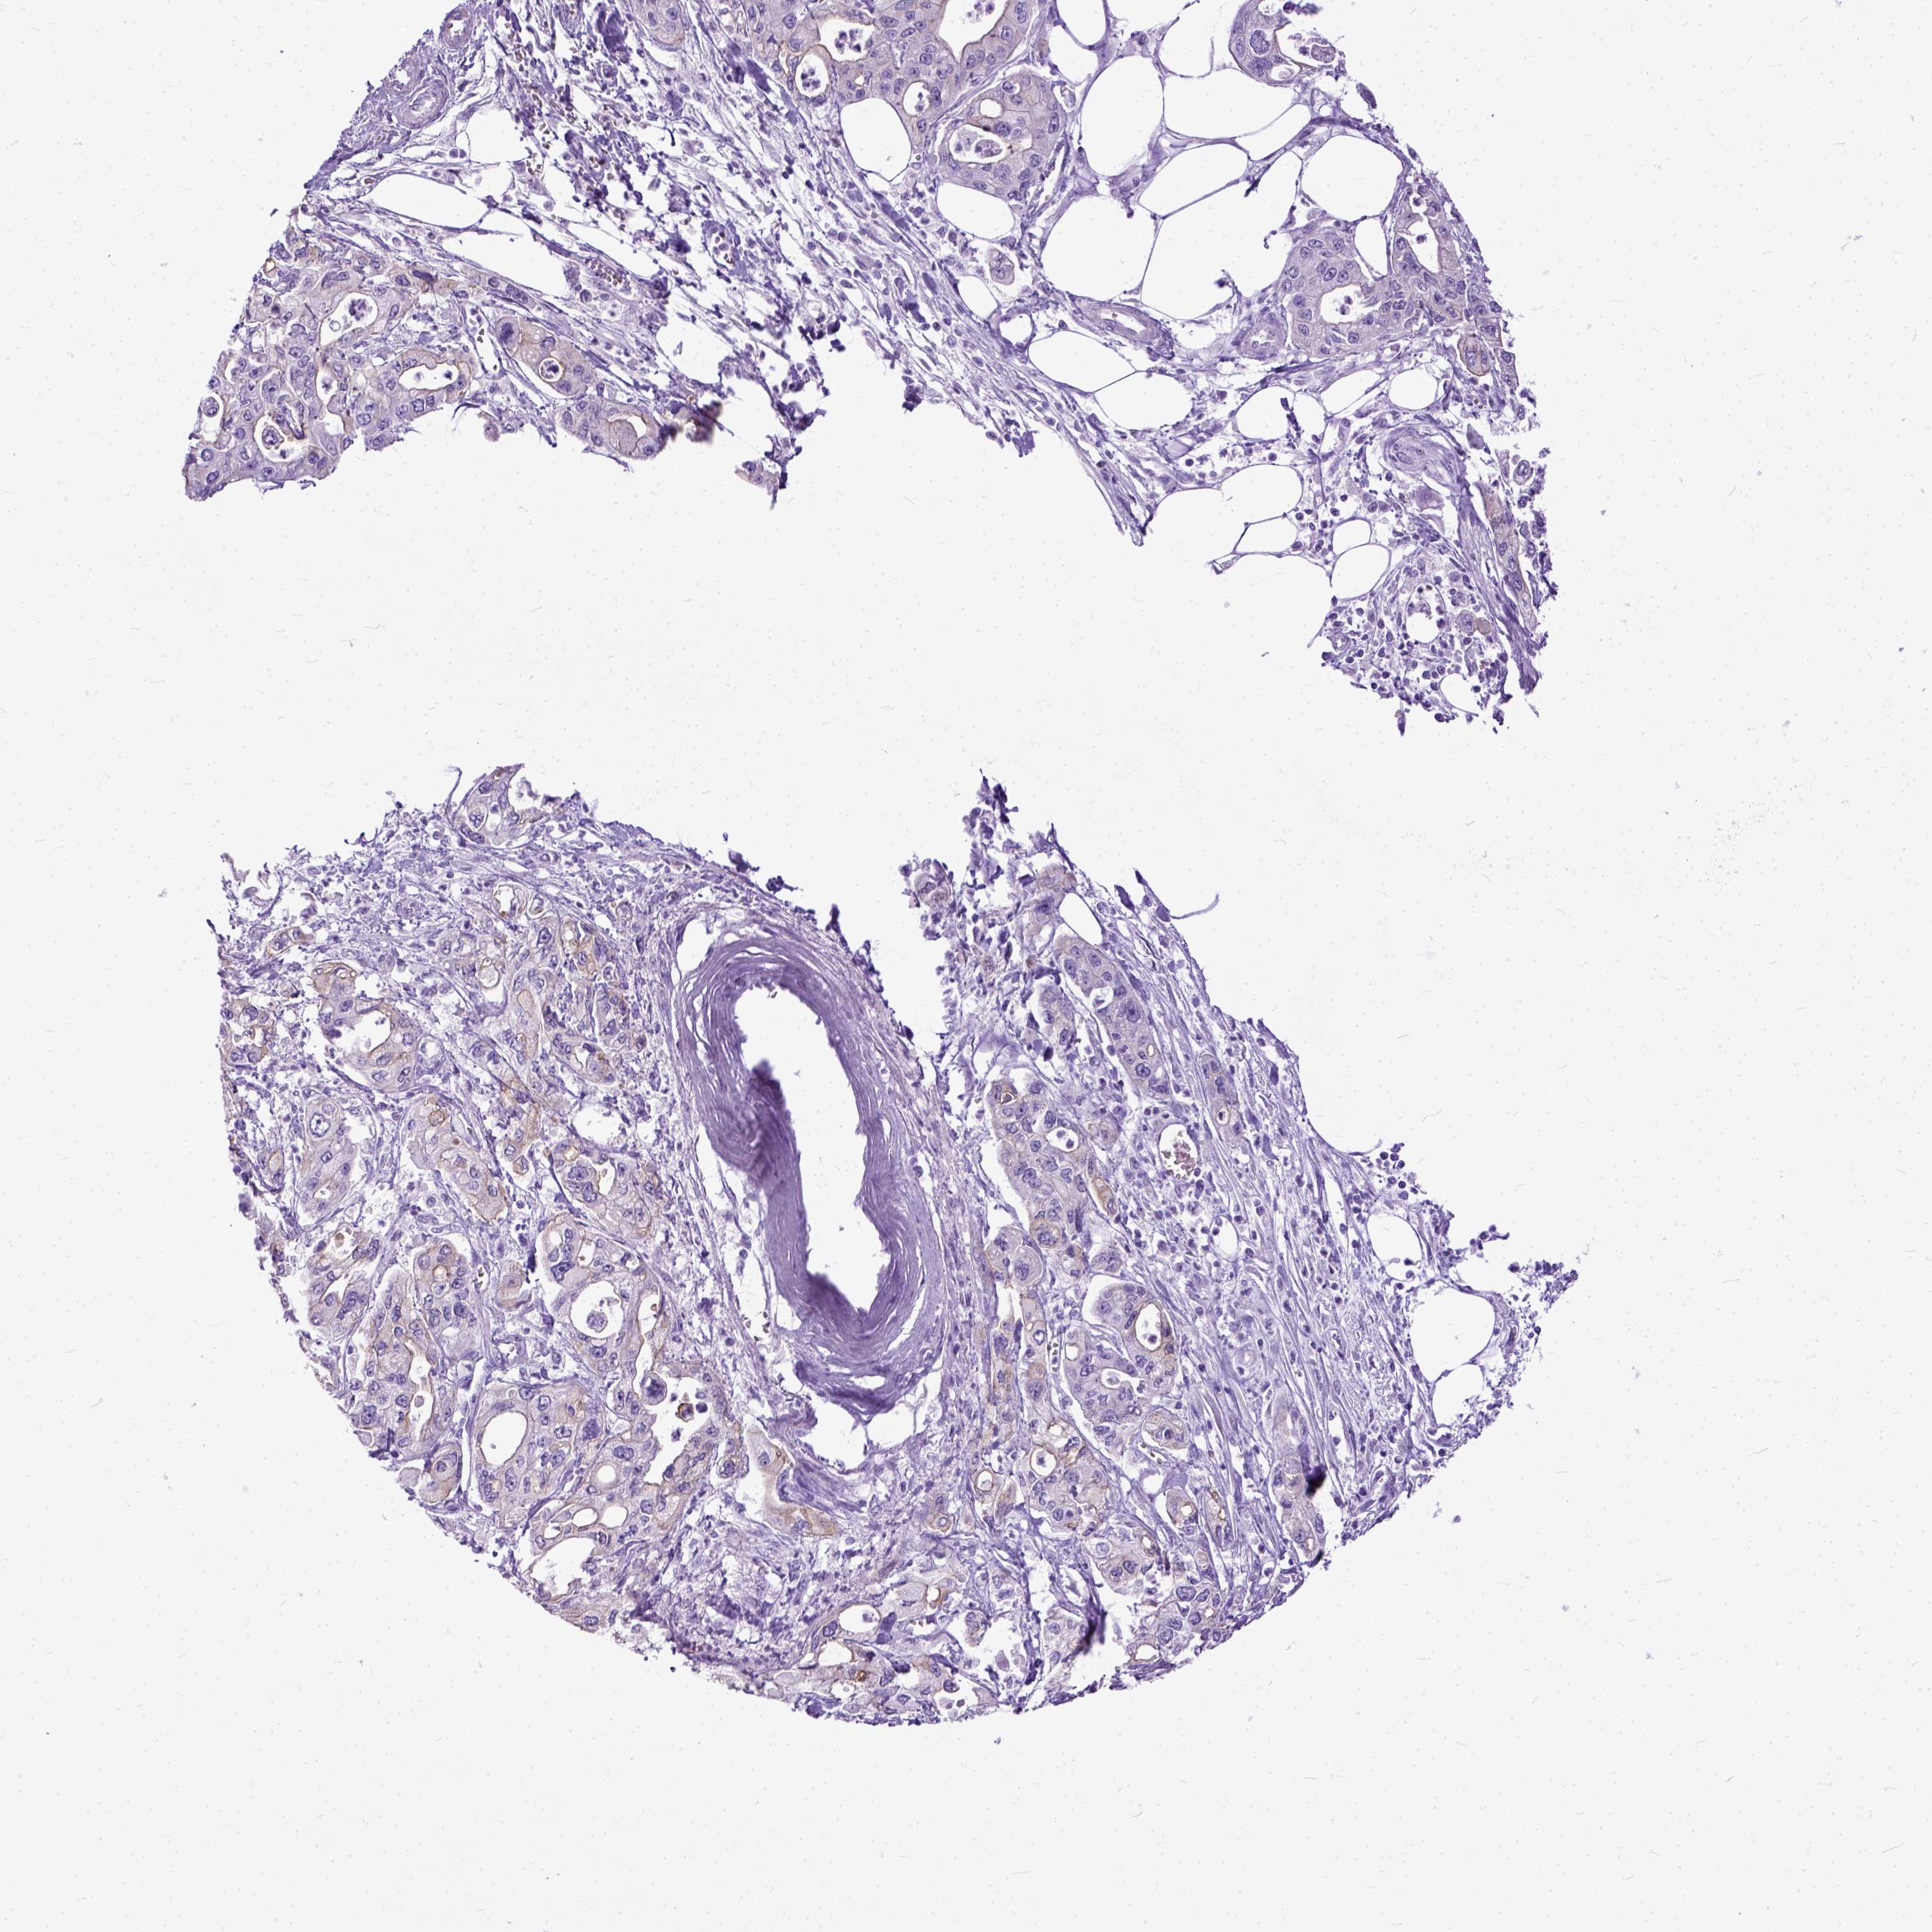

PANCREATIC CANCER - Protein expressioni

A mouse-over function shows sample information and annotation data. Click on an image to view it in a full screen mode. Samples can be filtered based on level of antibody staining by selecting one or several of the following categories: high, medium, low and not detected. The assay and annotation is described here.

Note that samples used for immunohistochemistry by the Human Protein Atlas do not correspond to samples in the TCGA dataset.

Antibody stainingi

Antibody staining in the annotated cell types in the current human tissue is reported as not detected, low, medium, or high, based on conventional immunohistochemistry profiling in selected tissues. This score is based on the combination of the staining intensity and fraction of stained cells.

Each image is clickable and will lead to virtual microscopy that enables deeper exploration of all samples and also displays staining intensity scores, fraction scores and subcellular localization as well as patient and tissue information for each sample.

Antibody HPA042550

Antibody HPA059859

Staining

High

Medium

Low

Not detected

Intensity

Strong

Moderate

Weak

Negative

Quantity

>75%

75%-25%

<25%

None

Location

Nuclear

Cytoplasmic/membranous

Cytoplasmic/membranous,nuclear

Adenocarcinoma, NOS